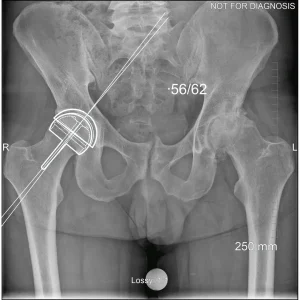

Hip resurfacing is a type of hip surgery used to treat hip arthritis, most commonly in younger and more active patients. Unlike a total hip replacement, hip resurfacing preserves more of your natural thigh bone. Instead of removing the entire femoral head (ball at the top of the thigh bone), the damaged surface is trimmed and covered with a smooth metal cap. The hip’s socket on the pelvis is also fitted with a metal cup.

Dr Grammatopoulos will review your X-rays and other imaging carefully to determine whether hip resurfacing is an appropriate option for you.

- Am I a candidate for hip resurfacing based on my X-rays and bone quality?